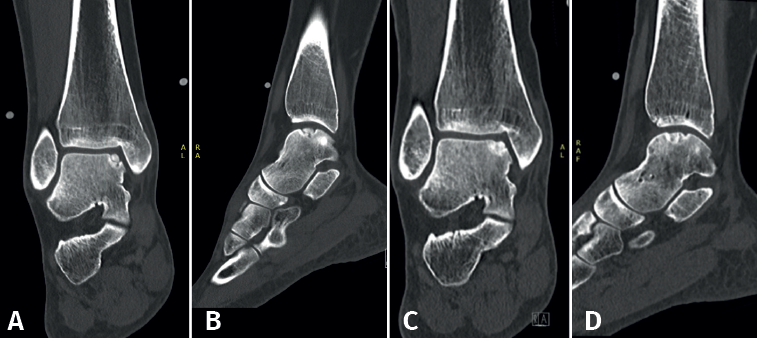

Fixation techniques have shown clinical and radiological success in 8 out of 10 patients, also maintaining their success in the long term (Figures 5 and 6). As these techniques preserve the hyaline cartilage and provide superior healing of the subchondral bone, they are advantageous over other surgical treatment options for OLTs, when feasible(39,41).

Fixation techniques

Fixation techniques are primarily applied to osteochondral lesions of the talus (OLTs) with fragmentary morphology. Consensus was that, for these techniques to be technically feasible, the lesion fragment should have a diameter of at least 10 mm and a depth of 3 mm(39). However, successful fixation has also been described for smaller lesions in studies using cortical bone pegs(40).

For acute displaced fragmentary lesions, fixation should be considered as the initial treatment(4). This should be performed as soon as possible to maximize healing potential and avoid further intra-articular damage(39). For chronic lesions, fixation can be applied when non-operative management is unsuccessful. As fixation techniques can provide superior subchondral bone healing(41), as well as preserving the overlying hyaline cartilage, it should be considered as the primary surgical treatment option when feasible.

Several fixation techniques using different materials have been described, including Kirschner wires, metal screws, bio-absorbable screws, bone pegs and/or fibrin glue(42,43,44,45). Fixation techniques may be performed arthroscopically when technically possible. The less invasive nature of arthroscopic fixation is theoretically advantageous. The most decisive factor for the possibility of arthroscopic fixation being the location/accessibility of the lesion. To achieve an adequate and stable fixation, the fragment needs to be fixated perpendicular to the talar dome. Therefore, the lesion must be located relatively anterior on the talar dome for arthroscopic fixation to be feasible(11). If arthroscopic fixation is not technically possible, it can also be performed as an open technique.